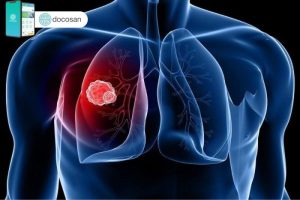

Ung thư phổi giai đoạn đầu làm sao nhận biết?

Ung thư phổi giai đoạn đầu cần được chẩn đoán, điều trị sớm thì kết quả điều trị sẽ tốt hơn, cải thiện tiên lượng sống còn của bệnh nhân. Tuy nhiên, bệnh nhân khi được chẩn đoán ung thư phổi đều đã ở giai đoạn muộn. Bài viết dưới đây của Doctor có sẵn […]